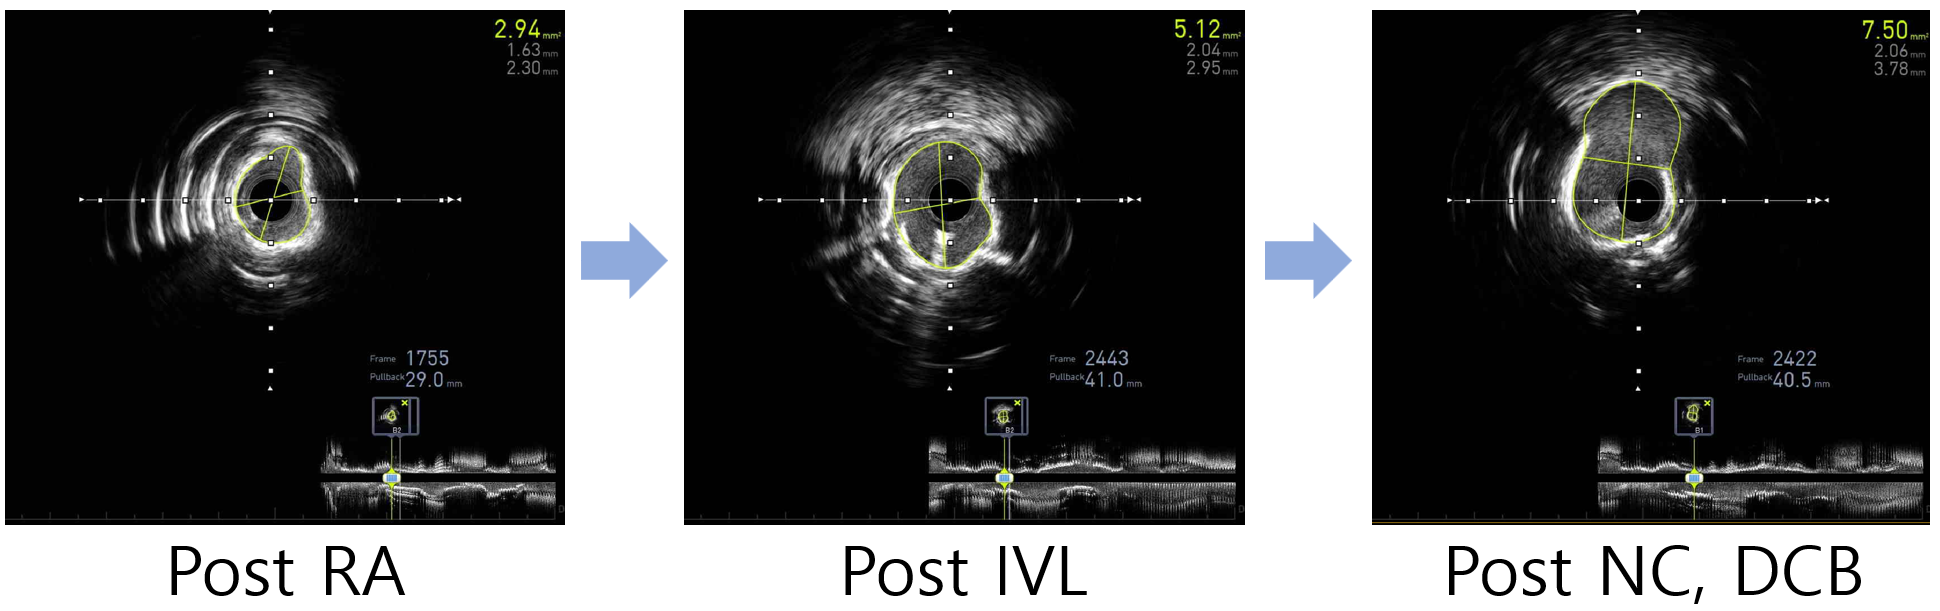

Coronary angiography demonstrated a heavily calcified, diffuse long disease in the mid to distal RCA. Initial intravascular ultrasound (IVUS) could not be advanced across the lesion due to the severe calcification. Without predilation with a non-compliant balloon, rotational atherectomy (RA) was performed using 1.25 mm and 1.5 mm burrs. Post-RA IVUS revealed circumferential (270¡Æ–360¡Æ) encircling calcium with some cracks, but lesion preparation was considered suboptimal.Subsequently, intravascular lithotripsy (IVL) was performed with a 3.0 ¡¿ 12 mm balloon, delivering 12 pulses to the segment that remained resistant to expansion. Follow-up IVUS demonstrated deep calcium fractures and an increase in the minimal lumen area (MLA) from 2.94 mm©÷ to 5.12 mm©÷. Angiography after IVL showed significant improvement in both flow and luminal narrowing.To further optimize the result, additional dilatation with a 3.5 ¡¿ 15 mm non-compliant balloon was performed, followed by drug-coated balloon angioplasty using a 2.5 ¡¿ 30 mm balloon. Final IVUS revealed an MLA of 7.5 mm©÷, and angiography confirmed an optimal result with no flow-limiting dissection.